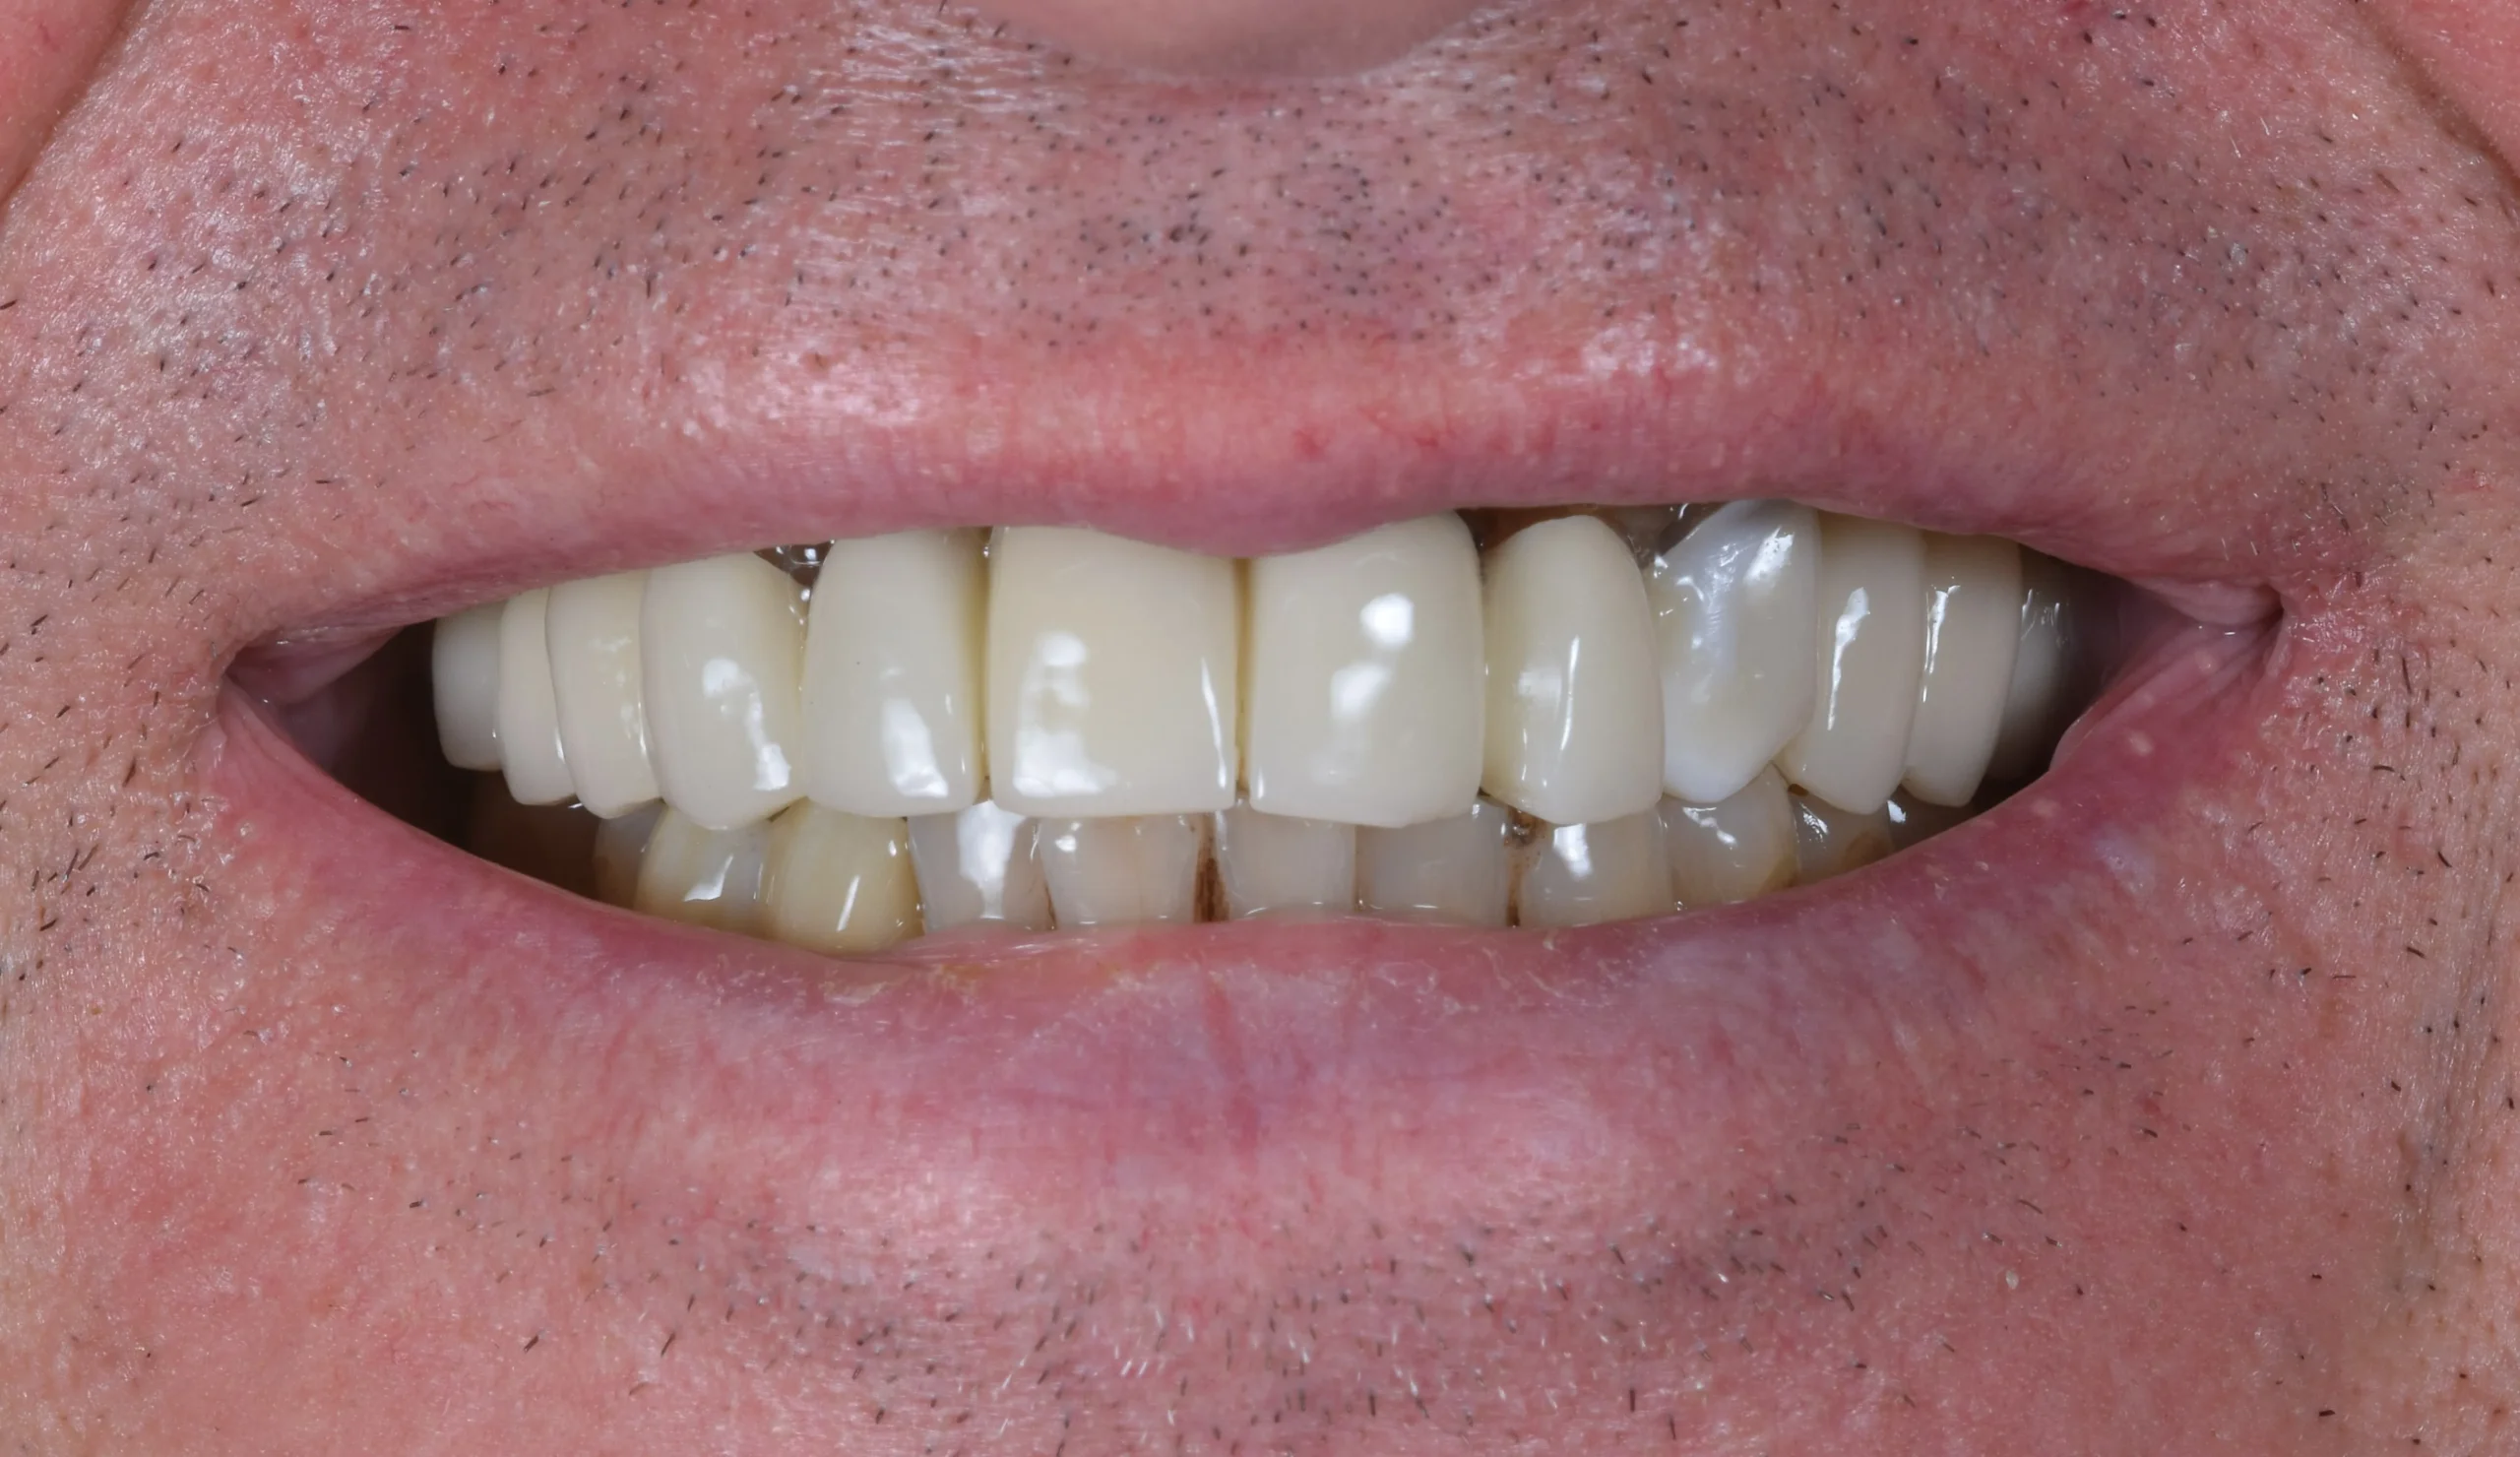

After 5 months of healing the implants were integrated in the bone and we provided the patient with his final teeth. A hybrid construction with titanium and zirconia was made. A functional, healthy and natural smile was achieved.

This kind of cases show us that using digital workflows in implant therapy makes our job more predictable and our life easier.Â